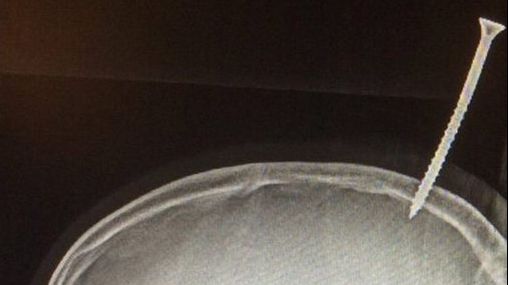

Caz medical înfricoșător: Un șurub de 15 cm a perforat creierul unui băiat de 13 ani

Un băiat din Salisbury, Statele Unite este norocos să se afle încă în viaţă după un accident bizar şi înfricoşător în care un şurub de 15 centimetri i-a perforat creierul.

Băiatul în vârstă de 13 ani, îl ajuta pe vărul său să construiască o casă într-un copac, moment în care a căzut, iar o scândură de lemn de 1,5 metri a căzut peste el. Aceasta a rămas fixată din cauza şurubului.

Şurubul nu a perforat doar craniul, ci şi creierul său, intrând în sinusul sagital superior. Vena se găseşte între cele două jumătăţi ale creierului şi scoate sângele din creier, ducându-l spre inimă, iar dacă este spartă, poate rezulta o hemoragie fatală.

"A fost la câţiva milimetri de a sângera până la moarte", a precizat chirurgul.

Pentru a putea fi transportat, paramedicii au fost nevoiţi să taie scândura, dar chiar şi aşa a fost greu de transportat. Conform descopera.ro, după şapte ore de la eveniment, specialiștii au reuşit să înlăture şurubul, fiind nevoie de o intervenţie chirurgicală extrem de delicată, care a inclus înlăturarea fragmentelor de os pentru a putea manipula şurubul.

Din fericire copilul a fost externat joi, 25 ianuarie, care se întâmplă să fie şi ziua în care împlineşte 13 ani.